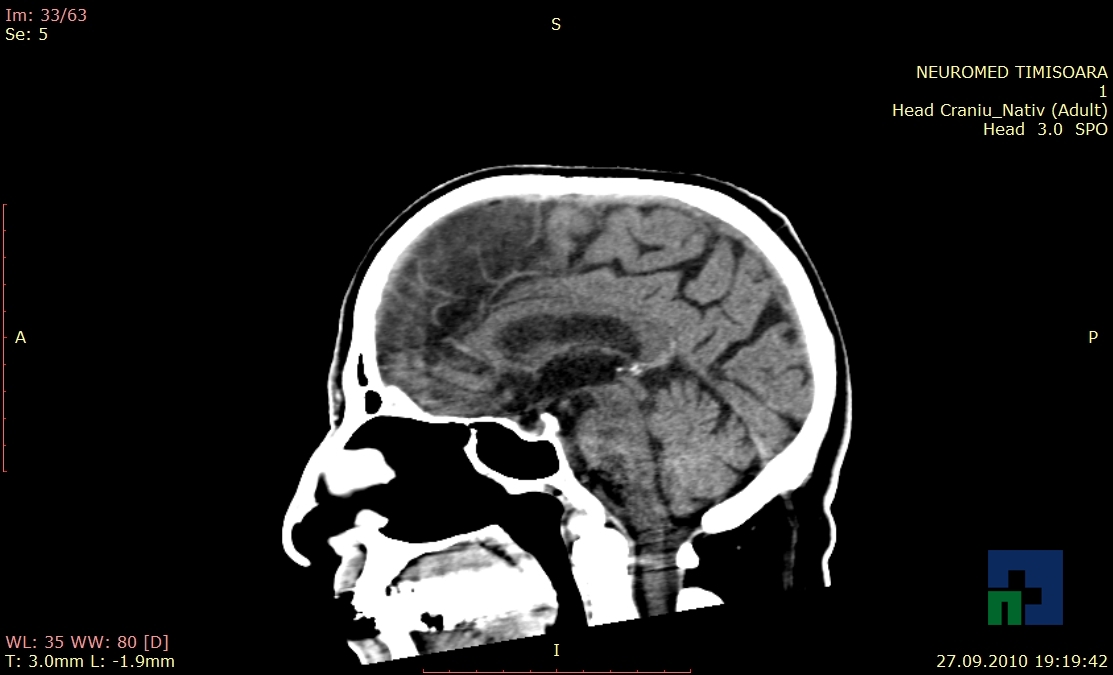

Examinare de rutină cerebrală, nativ și cu substanță de contrast (SDC) pentru diagnosticul:

- Accidentelor vasculare cerebrale ischemice sau hemoragice

- Tumorilor cerebrale

În cazul traumatismelor cranio-cerebrale:

- Evaluarea deplasării liniei mediane

- Evaluarea cisternelor perimezencefalice

- Diagnosticul edemului cerebral, a contuziei cerebrale, a leziunilor axonale difuze edematoase/hemoragice, a dilacerării cerebrale, a hematomului intraparenchimatos posttraumatic, a hematoamelor subdurale/extradurale (acute, subacute, cronice), a hemoragiei intraventriculare, a hemoragiei subarahnoidiene

- Diagnosticul traumatismelor de bază de craniu

- Diagnosticul fistulei LCR

- Diagnosticul herniilor cerebrale

- Diagnosticul fracturilor:

- Unice

- Multiple

- Cu înfundare

- Complexe cranio-sinusale

- Complexe cranio-etmoidale

- Complexe cranio-orbitare

- Complexe cranio-faciale

- Tumorilor cerebrale:

- Empiemul subdural

- Abcesul cerebral

- Fistula carotido-cavernoasa

- Higroma

- Atrofia cerebrală regională